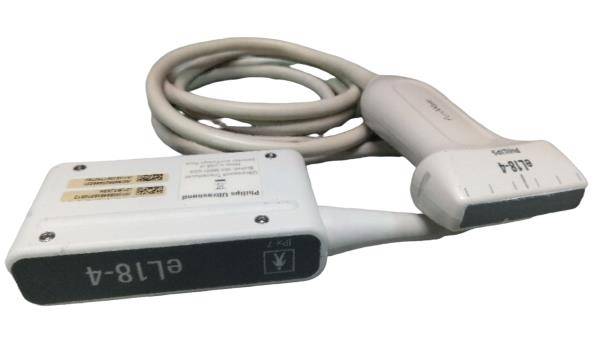

Veterinary Ultrasound KX5200 with Linear Rectal Probe

Veterinary Ultrasound KX5600V, Battery and Linear Rectal Probe